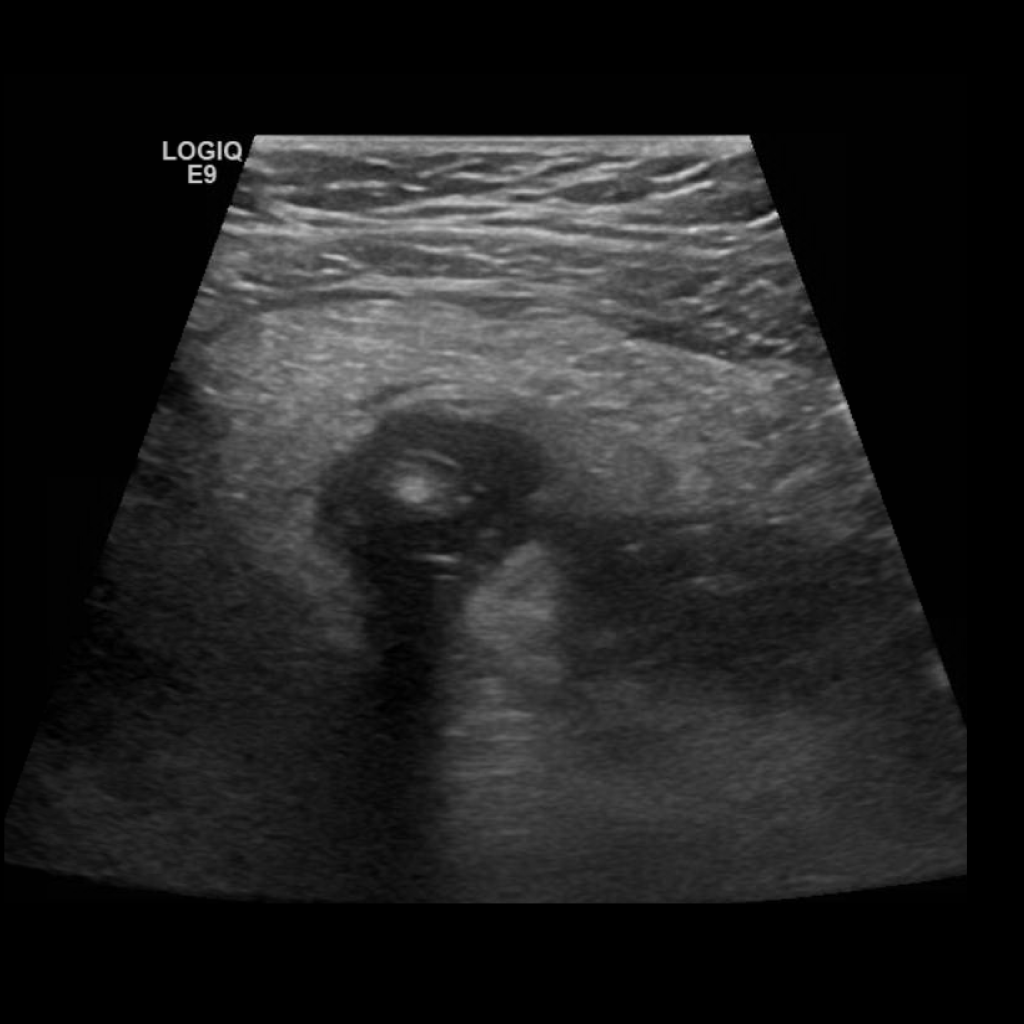

Appendicitis 4

1 cm appendicitis with hyperemia and appendicolith